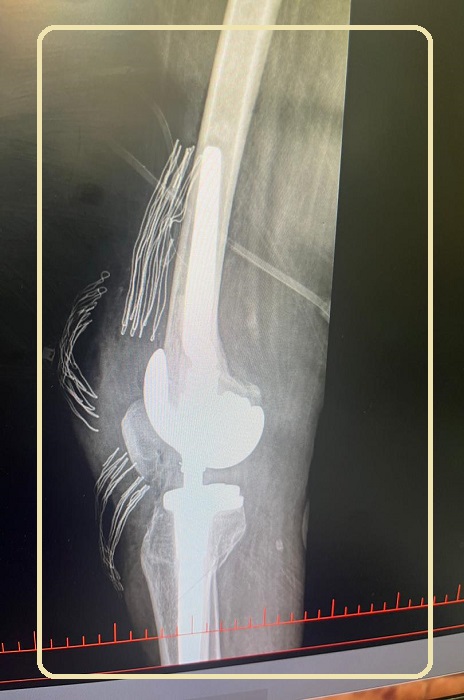

نخستین عمل جراحی تعویض مفصل زانو از نوع hinge در بیمارستان نفت امام خمینی (ره) توسط دکتر سپهر اسلامی با موفقیت انجام شد .

به گزارش پایگاه اطلاع رسانی بهداشت و درمان صنعت نفت آبادان ؛ سید علی پور محمد سرپرستار اتاق عمل بزرگ بیمارستان امام خمینی (ره) گفت : برای اولین بار در آبادان عمل تعویض مفصل زانو از نوع hinge برای بیمار 57 ساله با آسیب شدید لیگامانها به همراه استئوآرتریت توسط دکتر سپهر اسلامی متخصص ارتوپدی و با بیهوشی دکتر احمد رضا غلامی و پرسنل مجرب اتاق عمل با موفقیت انجام گرفت .